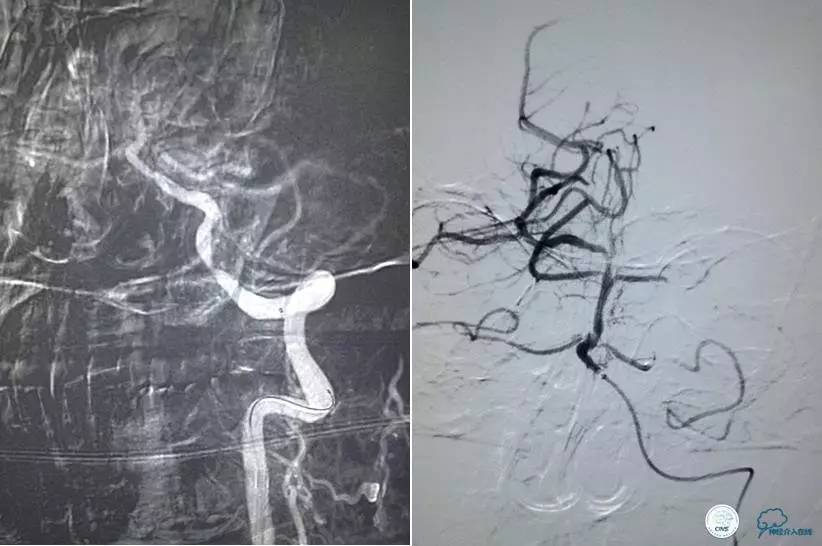

患者时间窗内,发病3h开始静脉溶栓。rt-PA9mg/kg,70mg,7mgIV;63mg微量泵注入1h。期间患者症状改善不明显。观察时间后,仍无改善。遂介入交接治疗。

2015-06-05脑血管造影:左侧颈内动脉闭塞。

评估患者侧支循环,考虑患者发病时间超过6个多小时,未行血管内治疗。